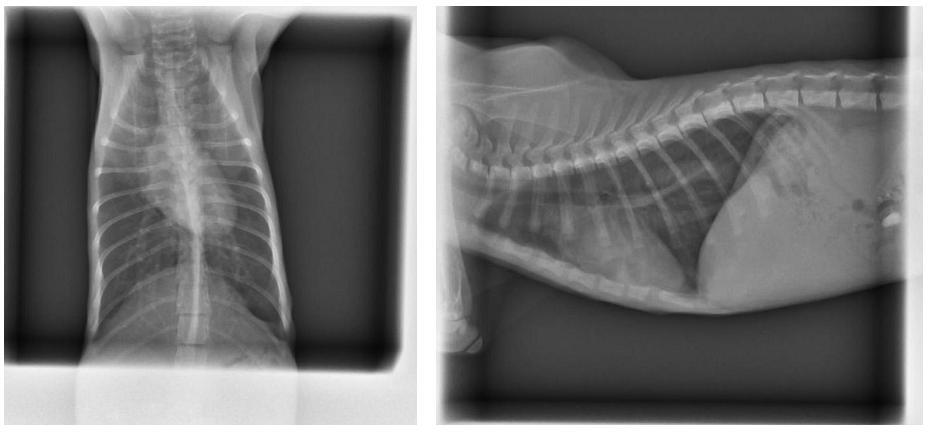

- 編號: 3713

主題: 車水馬龍道路邊的小幼貓 申請者姓名: Sally Chang 花色: 申請日期: 2013-12-30 23:58:08 申請者部落格: 申請者臉書網址: 所在縣市/合作醫院: 高雄市/恩澤動物醫院 治療費用: 6555元 需求人數: 8人 已結案 (2014-01-10 17:41:53) 報名人員: 鯉魚(已付款)、naifulei x7(已付款)、 候補人員: 動物病情說明: 這是參加送養會的途中,

送醫發現,

這枚小幼的有呼吸道感染的狀態,

精神狀況並沒有很好....

慎重起見...

幫小貓咪做了血檢,

發現數據沒有很好,

感緊又拍了X光發現,

有肺炎的狀況….

感緊上點滴投藥治療...

經過一週的療程,

小幼的狀況好轉許多...

目前也已經出院了到中途家安置,

醫療明細如下:

1.螢光染色 100*2

2.四環素眼藥膏 250(不折扣)

3.一周口服藥 500

4.血檢 900+600(二合一)

5.X-ray 400*2

6.點滴抗生素治療 600*3

7.住院費用 400*7

8.除蚤 250(不折扣)

9.噴霧治療 150*7

total 8650*0.7+500=6555動物近況說明: 小幼目前在中途家待送養!